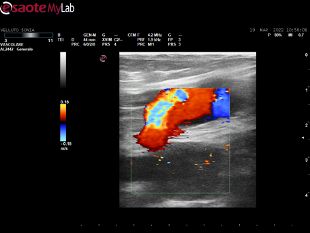

Svolgo attività quotidiana di diagnostica vascolare non invasiva, di cura delle arteriopatie e di tutte le patologie venose: varici, trombosi venose profonde acute, sindrome post-trombotica, ulcere venose e/o linfatiche, edemi degli arti inferiori, ulcere croniche.

• Ecocolordoppler vascolare

120 €